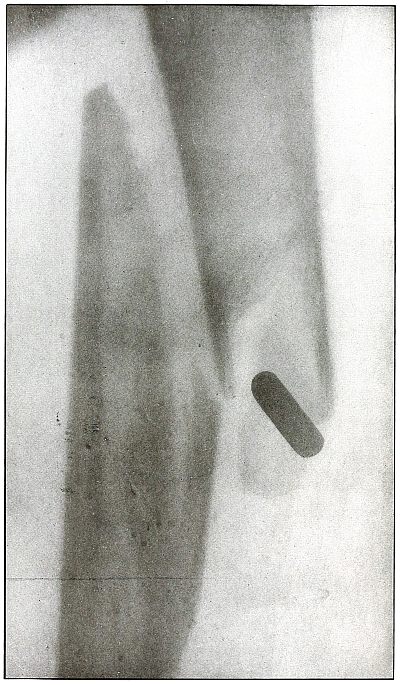

Plate 56.

[Pg 123]

Rifle—Plate 56.

LOWER EXTREMITY.

Gunshot Fracture Below the Middle of the Femur,

with Lodgment of the Bullet Near the Fracture.

The course of the projectile was transverse. The long splitting

fracture, with few large fragments and the lodged undeformed missile,

indicate that the injury to the bone was caused by the missile

striking the bone with large cross section or at an inclined angle so

that all of the remaining energy of the projectile at long range was

absorbed by the bone.

Had the point of the ball struck the bone with the same energy, it

would have produced smaller fragments and might then have passed

beyond the bone. The normal size of the diameter, slightly shortened

length, greater density of the point of the shadow, shows the bullet

to lie behind the bone with its nose pointing slightly backward. The

actual length of the bullet is 1.25 inches: the length of the shadow

is 1 inch.

Treatment and results would be about the same as in

plates 49 and 50.

[Pg 124]